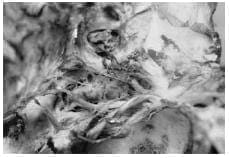

Fotografías de los especímenes disecados con referencia a los aspectos micro anatómicos descritos anteriormente:

2. Troncos vasculares dependientes de la A. Carótida Interna derecha intra cavernosos.

1-Tronco Meningo-Hipofisiario

2-Ramo Meníngeo Dorsal.

3-Tronco Infero lateral

4-VI par

5-Segmento Supraclinoideo

6- Segmento Subclinoideo. III, IV, V1 replegados.